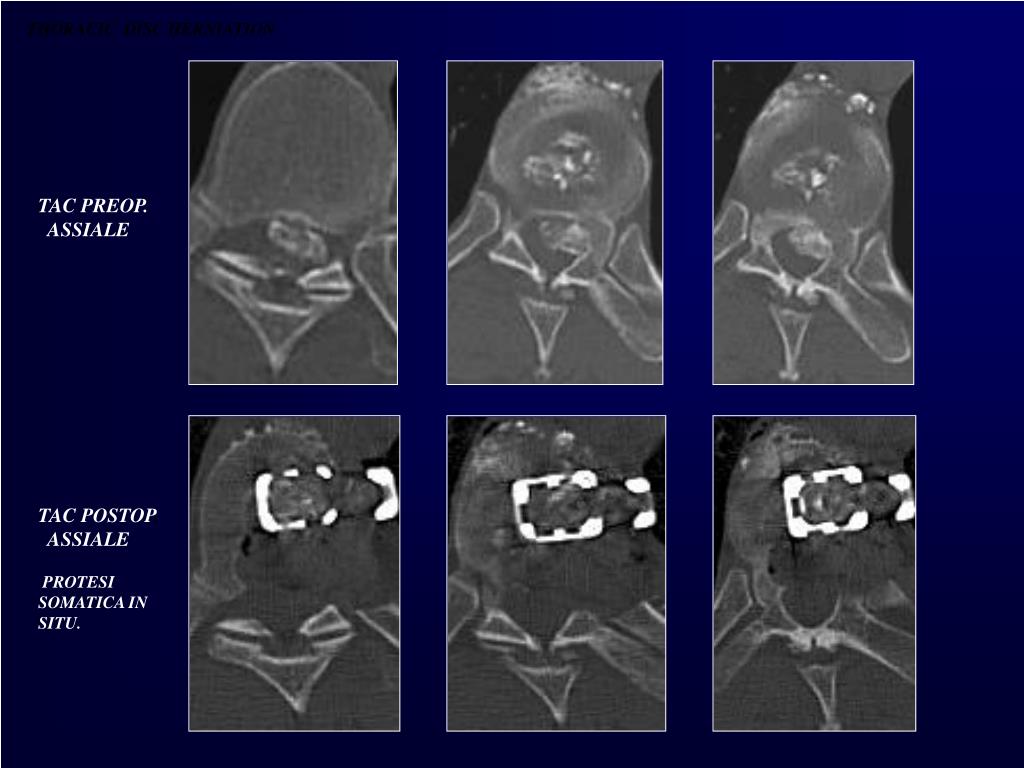

27. THORACIC DISC HERNIATION TAC PREOP. ASSIALE TAC POSTOP. ASSIALE PROTESI SOMATICA IN SITU.